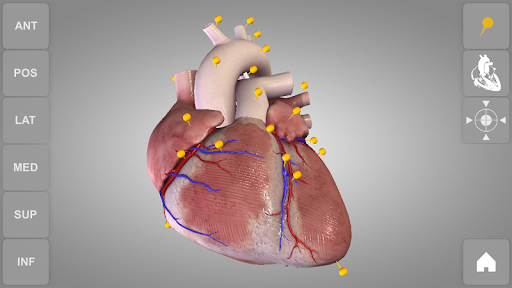

Heart 3D Atlas of Anatomy allows you to rotate a highly realistic 3D heart model as it was in your hands.

The human heart anatomical 3D model is revolvable in any direction giving a 360° view of the object.

Heart app is part of 3D Atlas of Anatomy collection, a human anatomy reference atlas for tablet and smartphone devices. The 3D medical models in these apps are similar to classic real plastic models but with the great benefits to be always available on your portable devices when you need them and occupy no physical space.

These apps can be of great help for students of medicine or to anyone who needs to study human anatomy shape in detail and from any angle. Immediacy and simplicity together with high quality are distinctive features of the app.